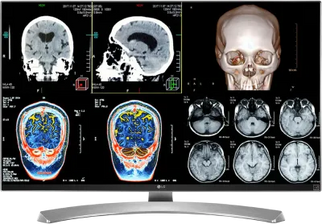

Best Selling Medical Displays

LG 27M-W 27" 8MP Color Clinical Review Medical Display Monitor (27M-W)

Barco Coronis Fusion MDCC-6430 6MP 30" Color LED General Radiology PACS Display

Barco Coronis Fusion MDCC-6530 6MP 30" Color Medical Diagnostic Radiology Monitor

LG 27" Color Fusion 8MP 4K LED Clinical Review Medical DICOM Display Monitor (27HS713C)

Barco Coronis Fusion MDCC-6330 6MP 30" Color LED General Radiology PACS Display

LG 8MP Fusion 4K 32" Color Medical Diagnostic Radiology Monitor 450 cd/m² DICOM Brightness (32HL512D-B)